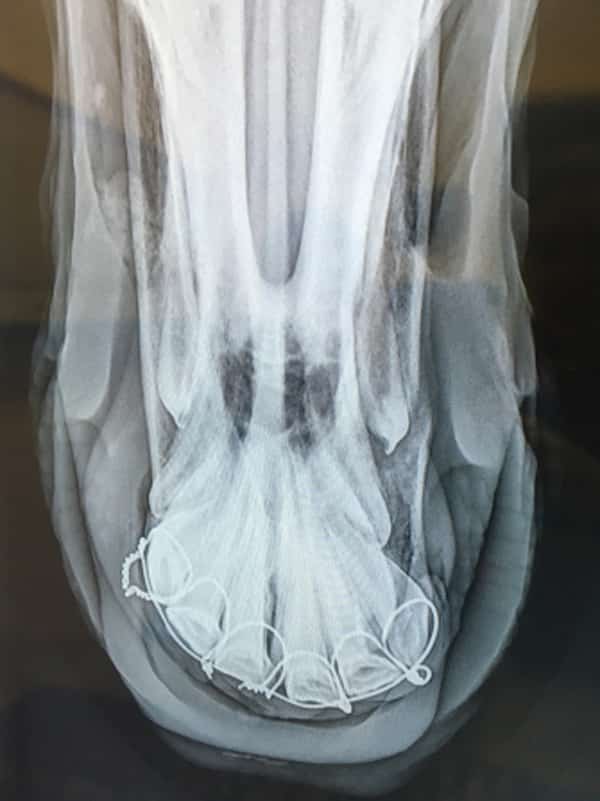

Coupled with this horrifying scene was the sight of Rory bleeding profusely from his mouth. He’d broken his upper jaw, beginning straight through his front teeth and traveling up through his jaw before ending towards the left. Michelle had no choice but to unload him on the side of the road and try to get him to a veterinarian as fast as possible. Rory remained calm in spite of his gruesome injury, allowing many different people to hold him amidst the chaos.

But Rory’s jaw fracture changed everything. On April 11, Dr. Sarah Dukti, DVM, DACVS, performed surgery at the Piedmont Equine Practice (Va.) to stabilize his mouth with wires. Like a teenager, Rory donned braces to reshape his jaw. He was prescribed stall rest and a specific diet with the hope that the wires could be removed around the end of June, if all continued correctly. And he wouldn’t be able to wear a bridle or bit until fall.